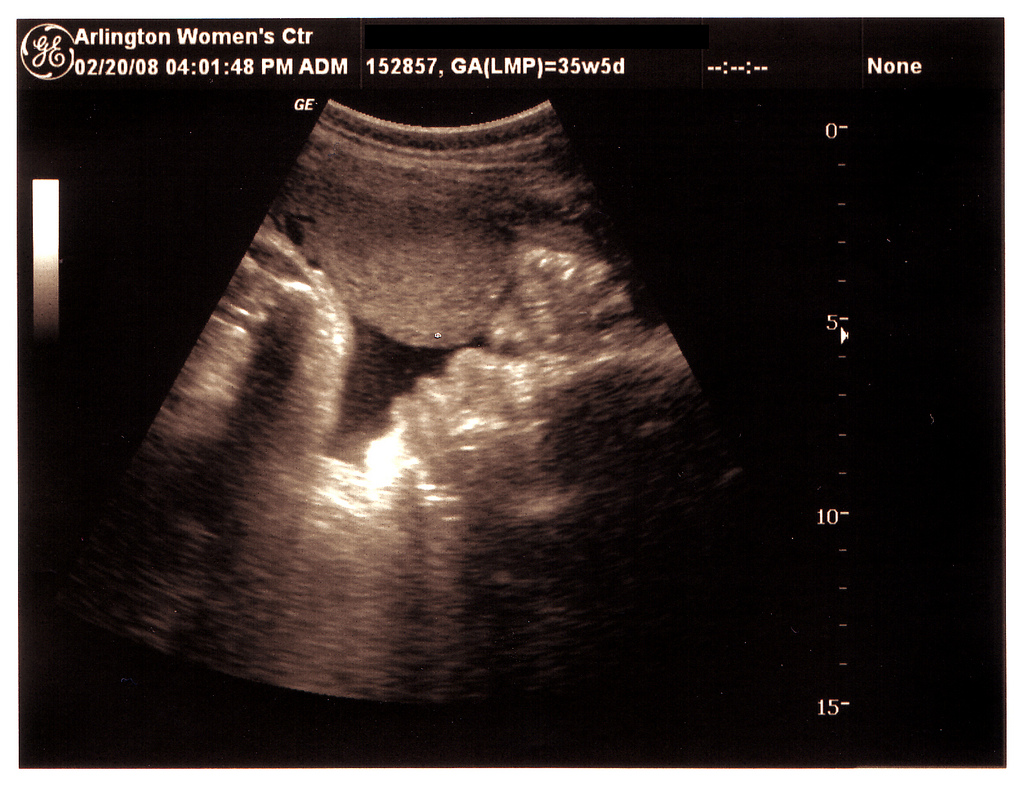

The legislation, cosponsored by 46 Republicans, would ban abortions after 20 weeks of pregnancy, with exceptions for instances of rape, incest, or critical health risks for the mother. Why 20 weeks? Fetuses can feel pain and can survive a premature birth at five months of development.